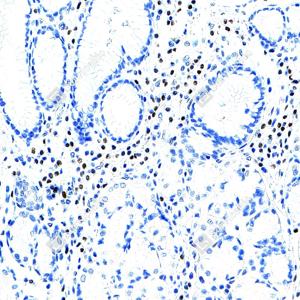

IHC检测RUNX2蛋白(货号 GB125631). 样品: 大鼠骨, 4%多聚甲醛 (货号G1101) 固定12-24小时. 抗原修复: 柠檬酸抗原修复液(干粉, pH 6.0) (G1201), 高压锅均匀喷气计时2分钟. —抗: 1: 500稀释, 4℃ 孵育过夜. 二抗: S-vision免疫组化多聚二抗(山羊抗小鼠), 即用型(货号G1301), 室温孵育20分钟. |